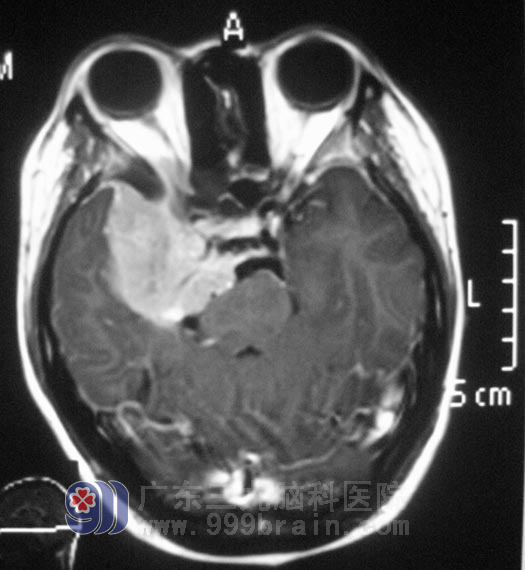

小李在2008年高考那年,出现右眼视力下降,以为是高负荷的复习迎考,造成视力出现问题。一年前右耳听力开始进行性下降,前十多天又出现了右耳失聪,外院行头颅MR检查提示:右侧眶内、中颅窝底、岩斜区占位,病变大小4.98cm×3.34cm×2.62cm,主要位于中颅窝,小部分累及后颅窝,脑干受压。

广东三九脑科医院综合神经外科 鲁明主任查阅影像资料发现:肿瘤侵润海绵窦,颅内外沟通,经CT检查见蝶骨及斜坡右侧、右侧颞骨岩部、额骨底部右侧骨质异常,经耳鼻喉科活检排除鼻咽癌。